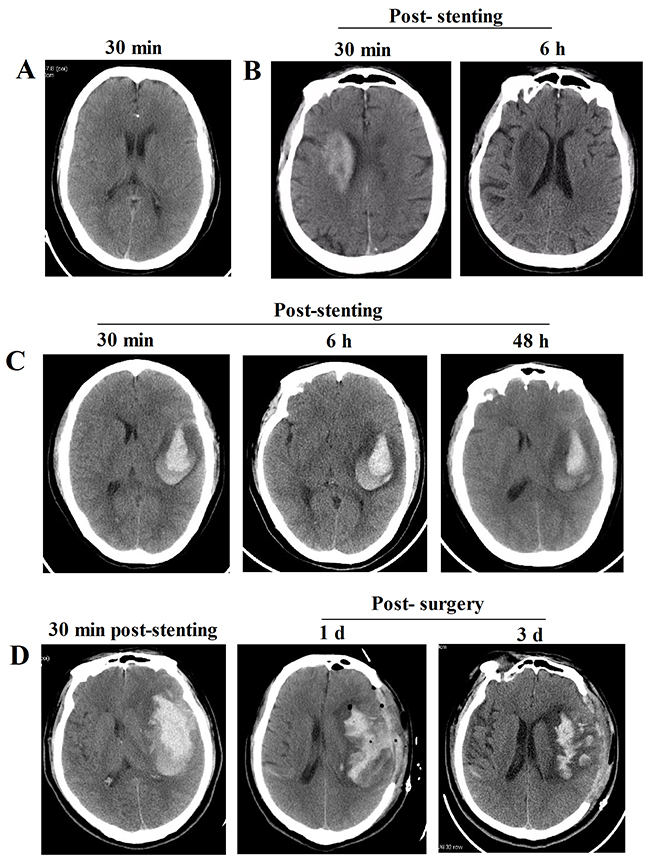

The features of the prompt head CT scans exhibited high-density shadows distributed range from brain parenchyma, subarachnoid spaces and ventricle. No high-density shadows existed in prompt CT scans were classified into Type I (Figure 1A), and the CT value was 16.35 ± 8.76 Hu. Additionally, the clinical features of prompt CT scans after stenting in Type II and III were summarized in Table 2. In Type II, the CT value was 92.27 ± 114.96 Hu, and the scope of the high-density shadow was less than the infarction areas and without mass effects; most of the shadow was evenly distributed and scattered into brain parenchyma or subarachnoid spaces, and closing to cortex (Figure 1B). While in Type III, the CT value was 268.5 ± 323.0 Hu, and the scope of the high-density shadows exceeded the infarction areas and with obvious mass effects; the irregularity high-density shadows were bilateral sometimes and scattered into brain parenchyma, subarachnoid spaces and/or ventricle (Figure 1C, 1D).

Figure 1: Representative images of the CT features in three Types after intracranial artery stenting. (A) Representative CT image of patients in Type I. (B) Representative CT images of patients in Type II show that high-density shadows existed at 30 min after stenting were gradually disappeared within the next 24h. (C) Representative CT images of patients in Type IIIa show that high-density shadows occured at 30 min, which was not expanded at 6 h post-stenting, while the high-density shadow was shrank at 48 h after stenting. (D) Representative CT images of patients in Type IIIb show that high-density shadows existed at 30 min after stenting were gradually aggravated with obvious mass effects within next 6 h, then immediately receiving surgical operation.

Following this strategy, all of the patients in Type I and Type II were have a better outcome following the treatment strategy (Figure 3). In the Type IIIa, although the prompt head CT scan of the patients exhibited mass effects after stenting, 11 of 14 patients who received conservative treatment had a relative better outcome withdrawing the DAPT and anti-coagulation drugs the high-density shadows stopped enlarging, while 3 of them exhibited worsen symptoms when discharged (Supplementary Table 1). However, 2 of 5 cases in Type IIIb were dead after the stenting due to severe cerebral hemorrhage despite of receiving surgical and medical treatment, while the other 3 patients had a relative better outcome (Supplementary Table 1).

During the operation, 150 - 300 mL contrast agent was used to observe the information of arterial stenosis and stent. Therefore, the prompt head CT scan would exhibit diverse CT features, for instance, some normal brain structures (including the cerebral artery and the upper sagittal sinus) are clearly enhanced after stenting and will disappear within next 24 h, which was the normal brain CT features not the cerebral hemorrhage. And we classified this into Type I, patients in which will continue to DAPT and anti-coagulation after stenting. Additionally, no high-density shadows in brain parenchymal and subarachnoid spaces are also deemed to normal features. While those high-density shadows scattered in the infarct areas without mass effects were classified into Type II. Although these features should also not be considered as cerebral hemorrhage, at the meaning time the DAPT and anti-coagulation treatment were continued in our study, the patients were treated into intensive care unit for 24 h with close monitoring. The head CT scan should be arranged at the next 6 h after stenting to further observe the situation of high-density shadows. Once the high-density shadows were increasing and/or occurred in mass effects and/or additional neurological signs, the DAPT and anti-coagulation drugs must be withdrawal, further head CT scan should be rearranged at the following 24 h after stenting based on the patients’ situation. If the prompt head CT scan exhibited high-density shadows with obvious mass effects, then immediately classified into Type III and withdraw all the DAPT and anti-coagulation drugs. Regarded to this type, previous reports showed that patients will receive the DAPT only after the hematoma was completely absorbed [24, 25]. While we first continued single anti-platelet (clopidogrel, 75 mg/d) treatment with close monitoring when the hematoma was stabilized showed by the 48-72 h post-stenting head CT scan, then we added the other anti-platelet drug (aspirin, 100 mg/day) with close monitoring if there was no expansion of hematoma within the next 5-7d (Figure 1C), because the DAPT was also critical important for the treatment of patients who underwent stenting 8. The data analysis found that our therapeutic strategy did not increase the re-bleeding risk, because 11 of 14 patients who received conservative treatment in Type IIIa had a relative better outcome although they experienced cerebral hemorrhage after stenting. However, when the cerebral hemorrhage companied with the tendency of brain hernia formation, the surgical intervention was suggested to save their life. It is a pity that 2 patients were dead although they received the surgical intervention due to the uncontrolled hemorrhage.